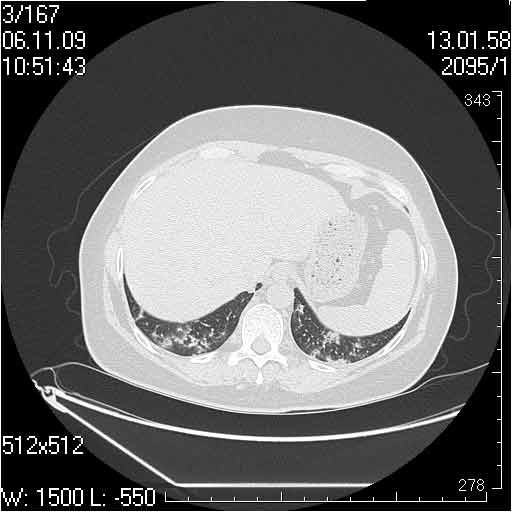

Случай №1

Женщина 50 лет.

Случай 1: изменения характерны для интерстициальной пневмонии (IIP/UIP idiopathic interstitial pneumonia/usual interstitial pneumonia); говорить о конкретной форме без открытой биопсии затруднительно.